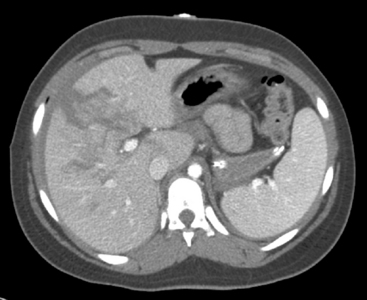

A pulmonary contusion is a bruise on the lung resulting from lung parenchymal injury. Although a pulmonary contusion can be asymptomatic and diagnosed only on CT scan, it can cause respiratory compromise following major blunt chest trauma.13,44 A significant pulmonary contusion will cause hypoxemia, and opacification is visible on a chest radiograph or CT scan (see Figs. 19-3, B and 19-4).

image

Fig. 19-4 Pulmonary contusion on chest radiograph and computed tomography (CT) scan. A, Chest radiograph. Note the increased opacification in the patient’s right lower lung fields (arrows). Note the absence of rib fractures. B, CT scan from the same patient demonstrating opacification (white contusion is visible in the dark air density) of the right lower lung. The trachea is not visible in mediastinum, so opacification is below the area of bifurcation of the trachea into bronchi. This CT view is shot from below the area of contusion with a view in the cephalad direction. The patient’s right chest appears on the left side of this image, and the patient’s left chest is visible on the right side of this image. The front of the patient is the top of this image, and the patient’s back is at the bottom of this image; thus, the patient’s heart is anterior (visible as a white oval) and vertebral column is posterior.

An associated hemothorax typically suggests the presence of a more severe lung injury. Treatment includes supplementary oxygen and may require positive-pressure ventilation with oxygen support and positive end-expiratory pressure.